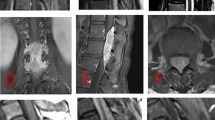

A 53-year-old man with no significant past medical history was admitted to our hospital because of pain in the lower-extremities and gait disturbance. His gait disturbance noticed by his family when he was 30 years of age. At age 51, he was found to have a spinal lipoma at a neighboring hospital and was referred to our institution. His lower extremity pain and gait disturbance worsened while he was under observation and he was admitted for further examination. Manual muscle testing revealed lower limb paresis that was more pronounced on the right side. The patellar tendon reflex was not exaggerated on either side, but the Achilles tendon reflex was hyperactive and the Babinski sign was positive on both sides. There was no evidence of bladder or bowel disturbance, and the lumbar JOA score was 10/29. MRI of the spine revealed a spinal lipoma at the L2/3 level and a flow void dorsal to the spinal cord at the level of the conus medullaris (Fig. 5). MRA revealed tortuous blood vessels within the spinal lipoma, as in Case 1 (Fig. 6). Subsequent angiography revealed an arteriovenous shunt from the right second lumbar artery. The radiculopial artery entered the spinal canal from its ventral aspect to form a arterio-venous shunt within the lipoma. A vein from the shunt region drained into the juxtamedullary vein within the spinal canal, and formed a congestion of the venous circulation (Fig. 7).

Case 2. MRA images taken with the TRICKS sequence shows tortuous blood vessels (white arrows) at the L2/3 level. This area is consistent with where this patient’s spinal lipoma was identified on T2WI (see Fig. 5)

Case 2 Angiogram showing an abnormal blood vessel with a shunt within the lipoma fed by the right second lumbar artery. The feeding artery (thick black arrow) is entering the lipoma from the ventral side, passing the shunt (white arrow), and then entering the spinal canal as the draining vein (thin black arrow)